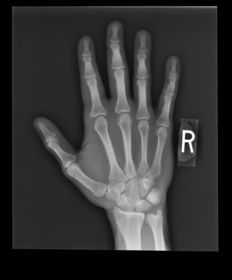

| PA Hand | ANATOMY: entire hand including 1'' of distal radius and ulna CRITERIA: equal concavity on either side of digits digits separated with no superimposition open joint spaces POSITIONING: CR perpendicular @ 3rd MCP joint |

| PA Hand | distal phalynxes are bent flatten hand to true PA *should be equal concavity on all digits* |

| PA Hand | obliqued - fingers are not equally concave on both sides distal metacarpals are overlapped |